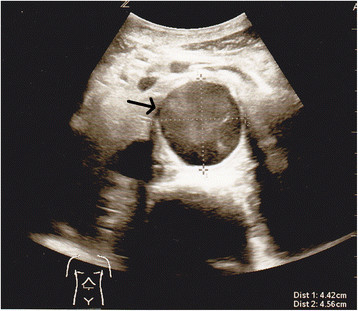

Abdominal aortic aneurysm without thrombus

| current | 18:11, 14 December 2015 | ![]() | 358 × 311 (200 KB) | Neil.m.young (Talk | contribs) | Abdominal aortic aneurysm without thrombus |